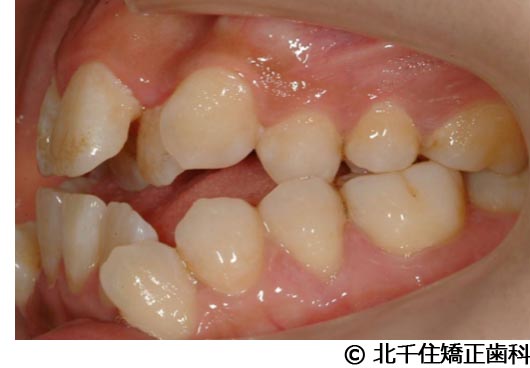

【症例5】上顎前突

- 治療前

- 治療後

- 治療名

- 上顎前突

- 費用

- 1,263,600円(税込)

- 期間

- 2年8ヵ月

- 治療回数

- 32回

- 通院頻度

- 1ヵ月ごと

- 年齢

- 13歳3ヵ月(初診時)

治療内容

-

患者様の症状

主訴:出っ歯

治療方法

骨格性の上顎前突、ヘッドギアを併用して上下顎第一小臼歯4本抜歯してワイヤー矯正。

治療結果

骨格性上顎前突に対し、ヘッドギアおよび抜歯を併用した矯正治療により歯列および咬合関係の調整を行った症例である。

治療後は保定装置を使用し、歯列および咬合の安定維持を目的として定期的な経過観察を行っている。

※治療結果は個人差があります。

治療を行う上での注意点(リスク・副作用)

歯磨き不良に伴うカリエスや歯周病、歯根吸収など。